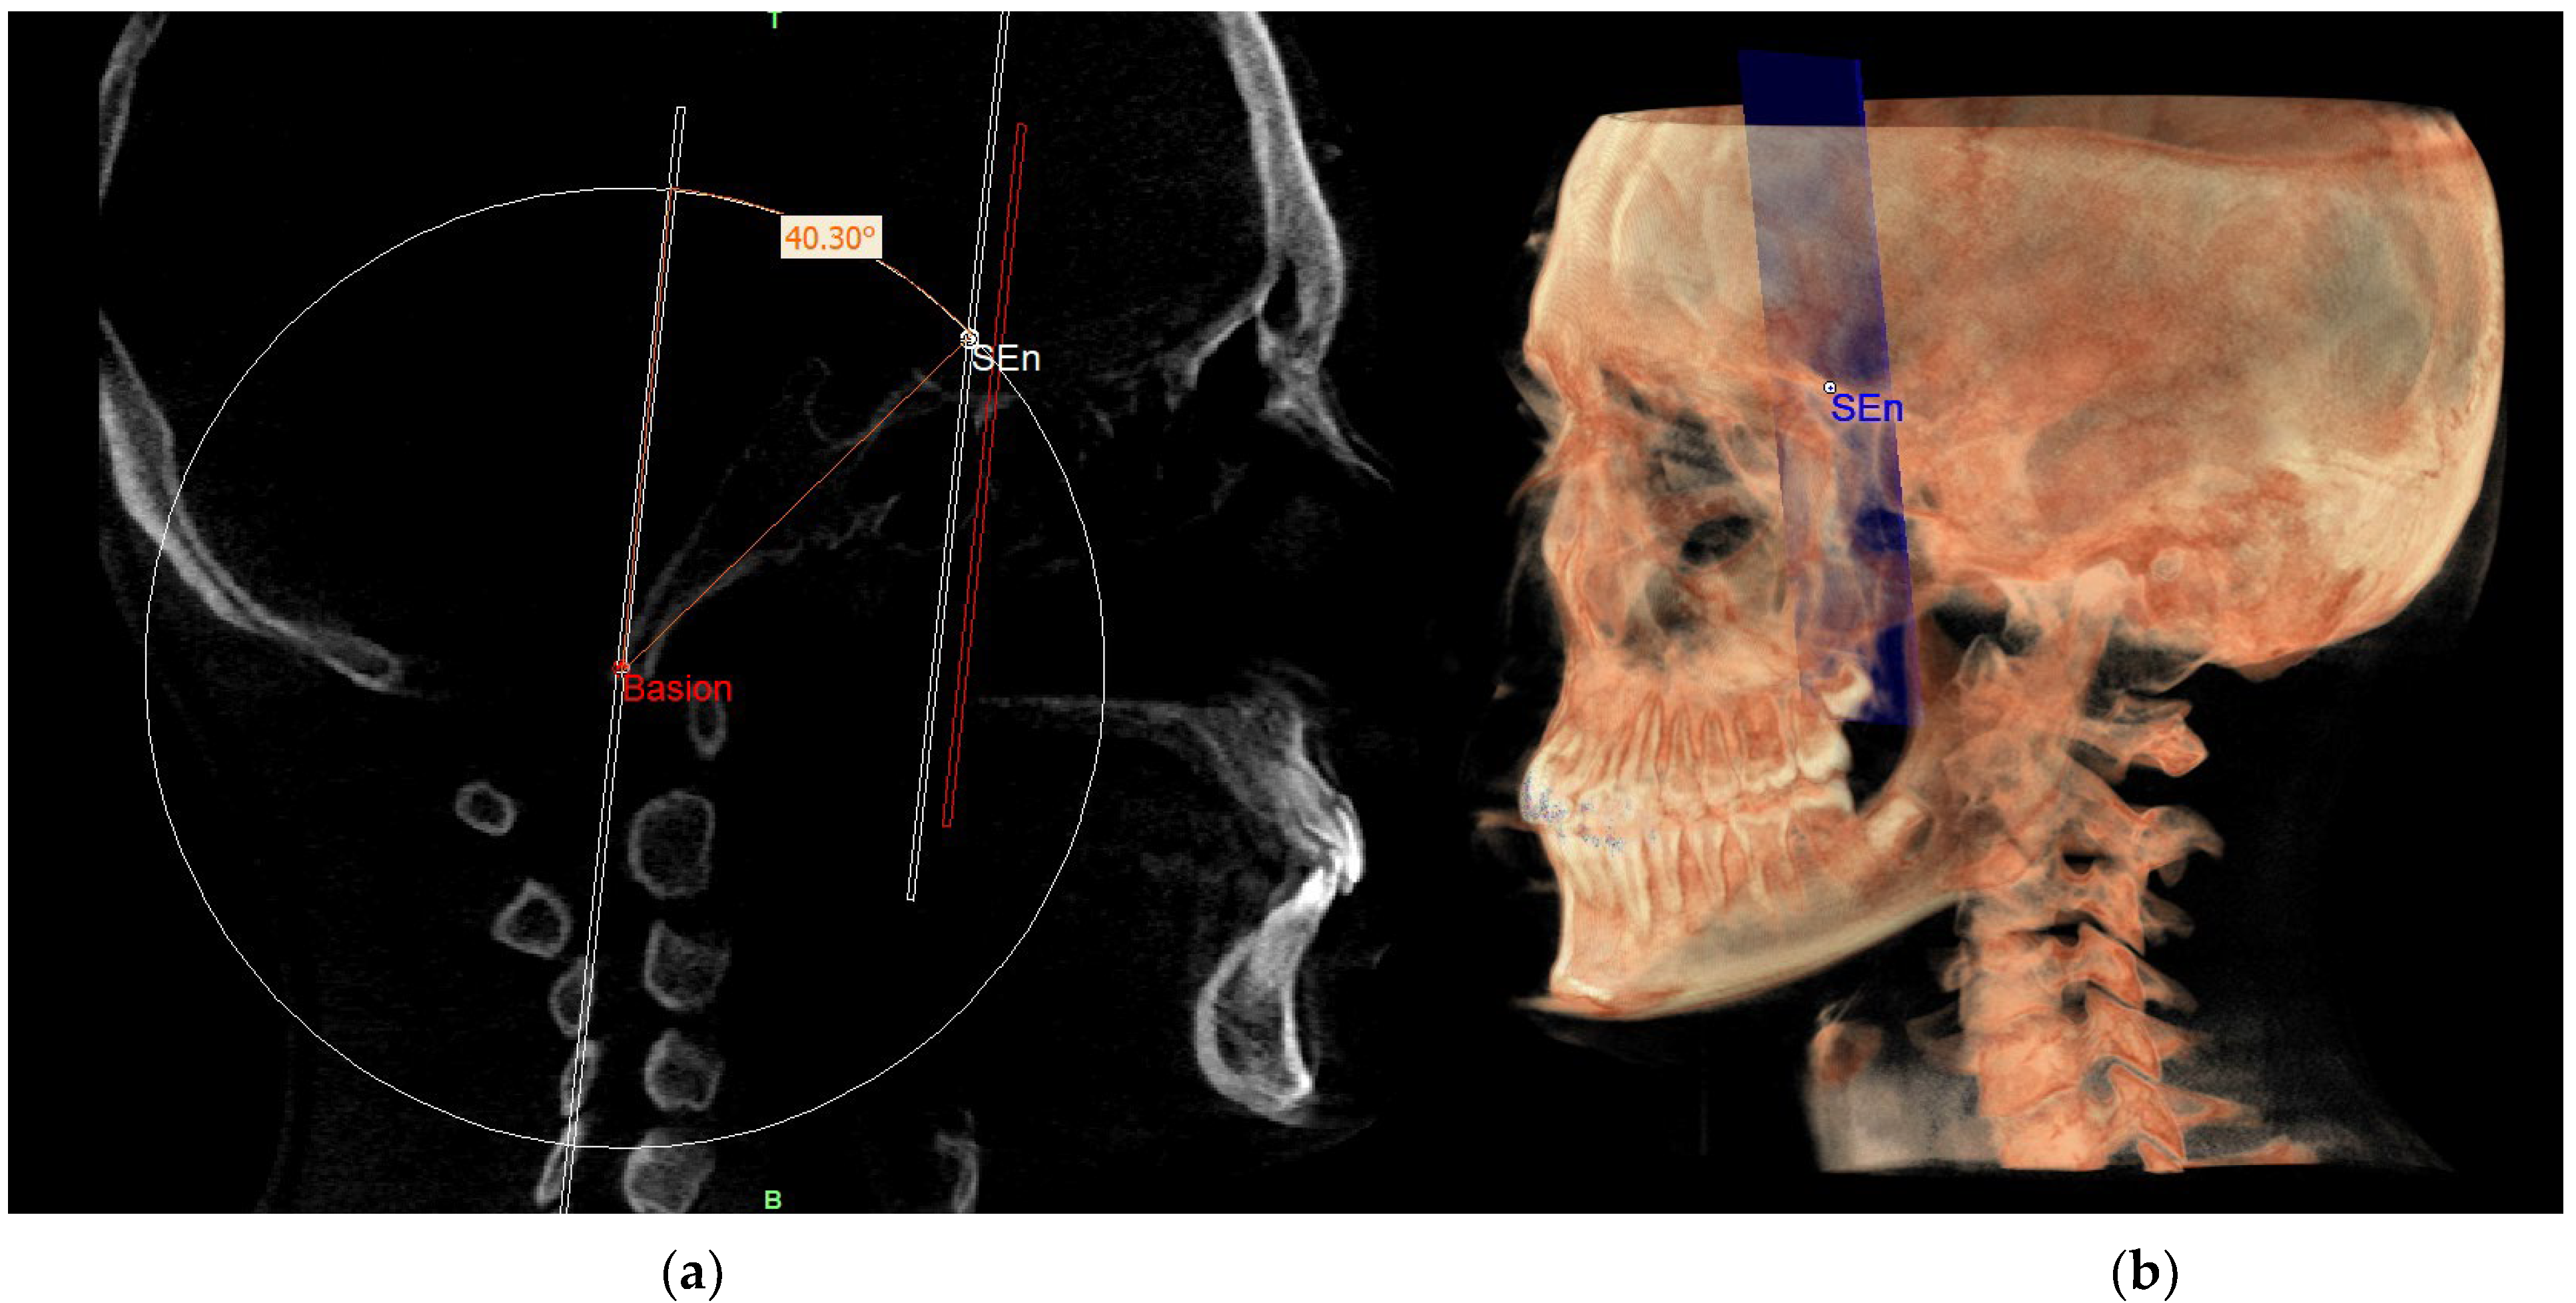

In order to localize the SEn point, the geometric construction rule of “parallel lines cut by a transversal line” was used: according to this rule, if two parallel lines are cut by a transversal one, alternate internal angles equal to each other are formed. Therefore, on the sagittal slice where the Ba point is located, we proceeded to trace a plane passing through Ba and parallel to the PM, defined as the construction plane through Ba (CPBa) (Figure 9).

This plan was not directly involved in the definition of the neutral 3D track but was used for the construction of the latter. In fact, an angle of 40.3° was built on this plane so that one side lies on the construction plane and the other side intersects with the circumference. The point of intersection with the circumference identified the SEn (Figure 10).

This point was used to draw the PMn plane which is parallel to the PM plane. In this way, CPBa and PMn represent two parallel lines cut by the BaSEn line and the internal angle that this latter forms with the PMn is 40.3° (Figure 11).

Figure 9. CPBa.

Figure 10. SEn.

Figure 11. PMn plane and SEn point in the sagittal view (a) and on volume rendering (b).